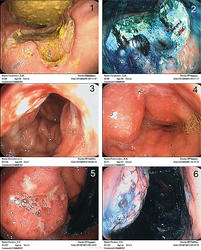

3. Подборка эндофото по ракам.

Эндофото опухолевых поражений желудка:

1 – блюдцеобразный рак антрума со стенозом привратника, 2 – то же, после окрашивания метиленовым синим и биопсии, 3 – эрозированный инфильтративный рак тела желудка, 4 – инфильтративный рак антрума, 5 – малигнизированная хроническая язва субкардии, 6 – то же после ХГС метиленовым синим

Эндофото опухолевых поражений желудка:

1 – экзофитный рак верхней трети тела желудка (вид в ретрофлексии), 2 – то же после ХГС индигокармином, 3 – кардиоэзофагеальный рак, ортоградный вид из пищевода, 4 – то же, ортоградный вид кардии, 5 – то же, ретроградный вид кардии, 6 – то же, после ХГС метиленовым синим